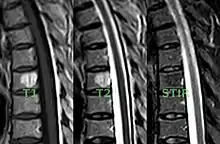

T1, T2, and STIR MRI images of a vertebral hemangioma

MRI

Baudrez, Galant, and VandeBerg found that MRI appearance is dictated by histology of the tumor-like lesion—Vascularity, interstitial edema, and interspersed fat.[15] The presence of high or moderate signal intensity on both T1 and T2 images is related to the ration of fat to vessels and edema. For example, a VH with a high concentration of fat and a relatively low make-up of vessels and edema would show a high signal intensity on T1-weighted spin-echo images and intermediate signal intensity on T2-weighted fast spin echo images. Whereas a VH made-up of nearly equal portion of fat and vessels and edema would show intermediate signal intensity on T1-weighted images and high signal intensity on T2-weighted images.[15]